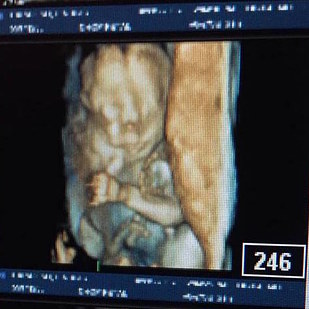

“We wanted her no matter what,” Paradiso said, so they planned to wait until Omara was viable at 27 weeks to deliver her surgically so doctors could operate on the tumor, which ensured the best chance of survival.

“We had to have her delivered early by an EXIT procedure, which is basically like a larger and riskier C-section, because her tumor was so massive that at 27 weeks she would be too big to deliver vaginally,” Paradiso said.